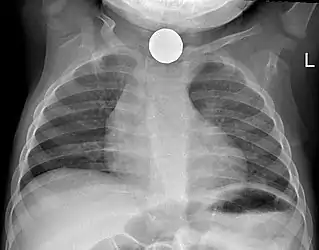

Chest X-ray showing a Canadian dollar coin in the esophagus of a young child

Prior to undertaking endoscopy, attempts should be made to locate the foreign body with x-rays or other non-invasive techniques.[1] For radio-opaque objects, x-rays of the neck, chest and abdomen can be used to locate the foreign body and assist endoscopy.[9] Alternative approaches, including the use of metal detectors, have also been described.[10]

X-rays are also useful for identifying the type of foreign body ingested and complications of foreign body ingestion, including mediastinitis and perforation of the esophagus.[1]